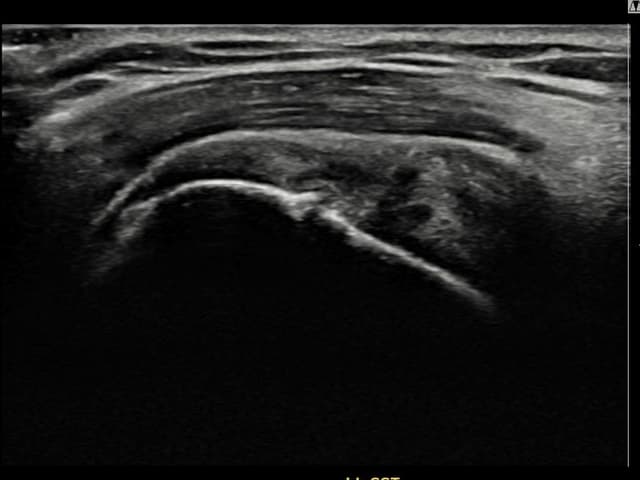

[촬영시기:22.10.18]

[석회분쇄흡입술] 우측 어깨 통증과 운동 제한으로 일상생활이 불편해진 30대 여성 환자로, X-ray에서 우측 극상근건 내 석회 침착이 확인되어 석회분쇄흡입술을 시행하였습니다.